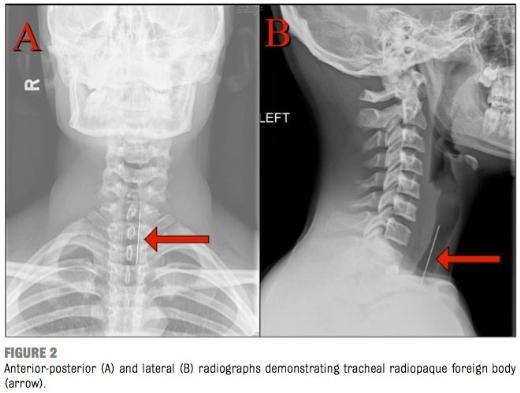

5. 15 yaşındaki bir çocuğa ait olan bu röntgende ise üflemeli tabancayla fırlatılan iğnenin boğazına nasıl saplandığı görülüyor.

15 yaşındaki bir çocuğa ait olan bu röntgende ise üflemeli tabancayla fırlatılan iğnenin boğazına nasıl saplandığı görülüyor.